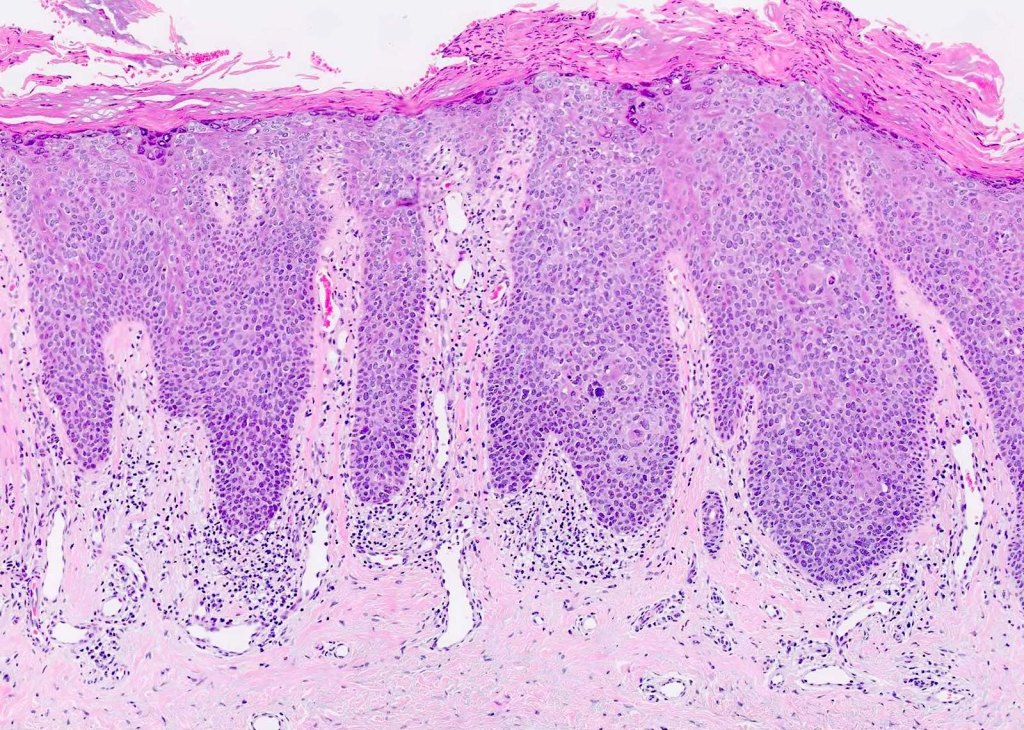

Sections show buccal mucosa in which there is mild epithelial atrophy with parakeratosis. The pattern of epithelial maturation is regular and the overall architecture is preserved. The rete processes are flattened and bands of hyaline collagen best seen in Van Geison stained sections are present in the lamina propria. A mild chronic inflammatory infiltrate is present in the subepithelial tissue.

The buccal mucosa seems to be undergoing a transformation – a mild epithelial atrophy. It’s as if the cells are shrinking, losing some of their vitality. Parakeratosis is in play too, where these cells are holding onto their nuclei longer than they should. It’s like they’re not quite ready to grow up and shed their immature ways.

Despite the changes, the overall architectural blueprint of the buccal mucosa remains intact. The maturation of the epithelial cells follows a regular pattern, almost like well-practised dancers performing a choreographed routine. The rete processes – the finger-like projections that interlock the layers – appear flatter than usual. It’s as if they’re tired and can’t stand as tall as they used to.

Ah, now for a fascinating twist! Van Geison stained sections reveal bands of hyaline collagen lurking in the depths of the lamina propria – the supporting layer beneath the epithelium. These collagen bands are like secretive cobwebs, weaving a mysterious tale of their own. Their presence hints at something more profound beneath the surface.

As our investigation deepens, we stumble upon an unexpected guest – a mild chronic inflammatory infiltrate. It’s almost like a small group of protesters voicing their concerns beneath the epithelial cityscape. What could they be protesting? What’s causing this subtle turmoil?

Now, my fellow detectives, armed with our clues and insights, it’s time for the big reveal! The answer to this intriguing riddle is none other than Submucous Fibrosis.

Submucous Fibrosis is a condition often linked to the chewing of paan (betel), a common practice in certain cultures. In this condition, dense collagenous bands sneakily weave their way into the lamina propria – that’s the collagen we spotted earlier! These bands tighten their grip, causing limitations in mouth opening and even trouble with swallowing.